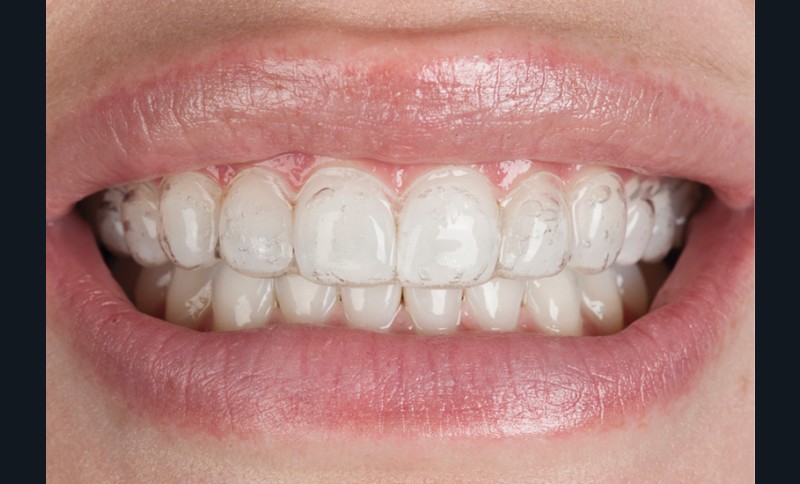

L’éclaircissement dentaire peut être réalisé à domicile (technique ambulatoire) à l’aide de gouttières porte-gel sur mesure fabriquées après prise d’empreinte (fig. 1), ou au cabinet par application de gel après isolation et protection des tissus mous (fig. 2).